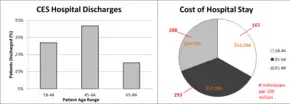

The most frequent injuries of the thoracolumbar region are to the conus medullaris and the cauda equina, particularly between T12 and L2.[13] Of these two syndromes, CES is the more common.[13] CES mainly affects middle-aged individuals, particularly those in their forties and fifties, and presents more often in men.[13][14][26] It is not a typical diagnosis, developing in only 4 to 7 out of every 10,000 to 100,000 patients, and is more likely to occur proximally.[12][13][14] Disc herniation is reportedly the most common cause of CES, and it is thought that 1 to 2% of all surgical disc herniation cases result in CES.[12][13]

CES is often concurrent with congenital or degenerative diseases and represents a high cost of care to those admitted to the hospital for surgery.[13][26] Hospital stays generally last 4 to 5 days, and cost an average of $100,000 to $150,000.[26] Delays in care for cauda equina results in the English NHS paying about £23 million a year in compensation.[27]